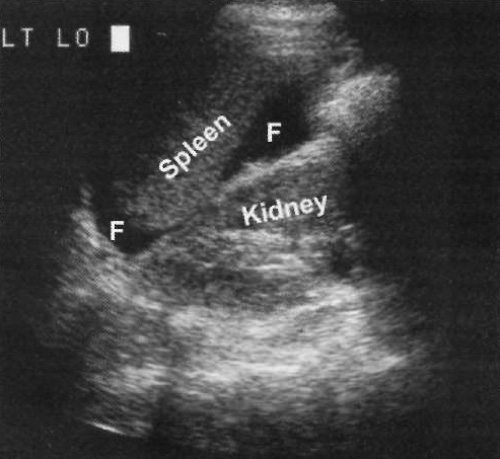

Фото 5. Жидкость в левом верхнем квадранте живота. Продольное ультразвуковое изображение демонстрирует жидкость (F) между почкой и селезенкой